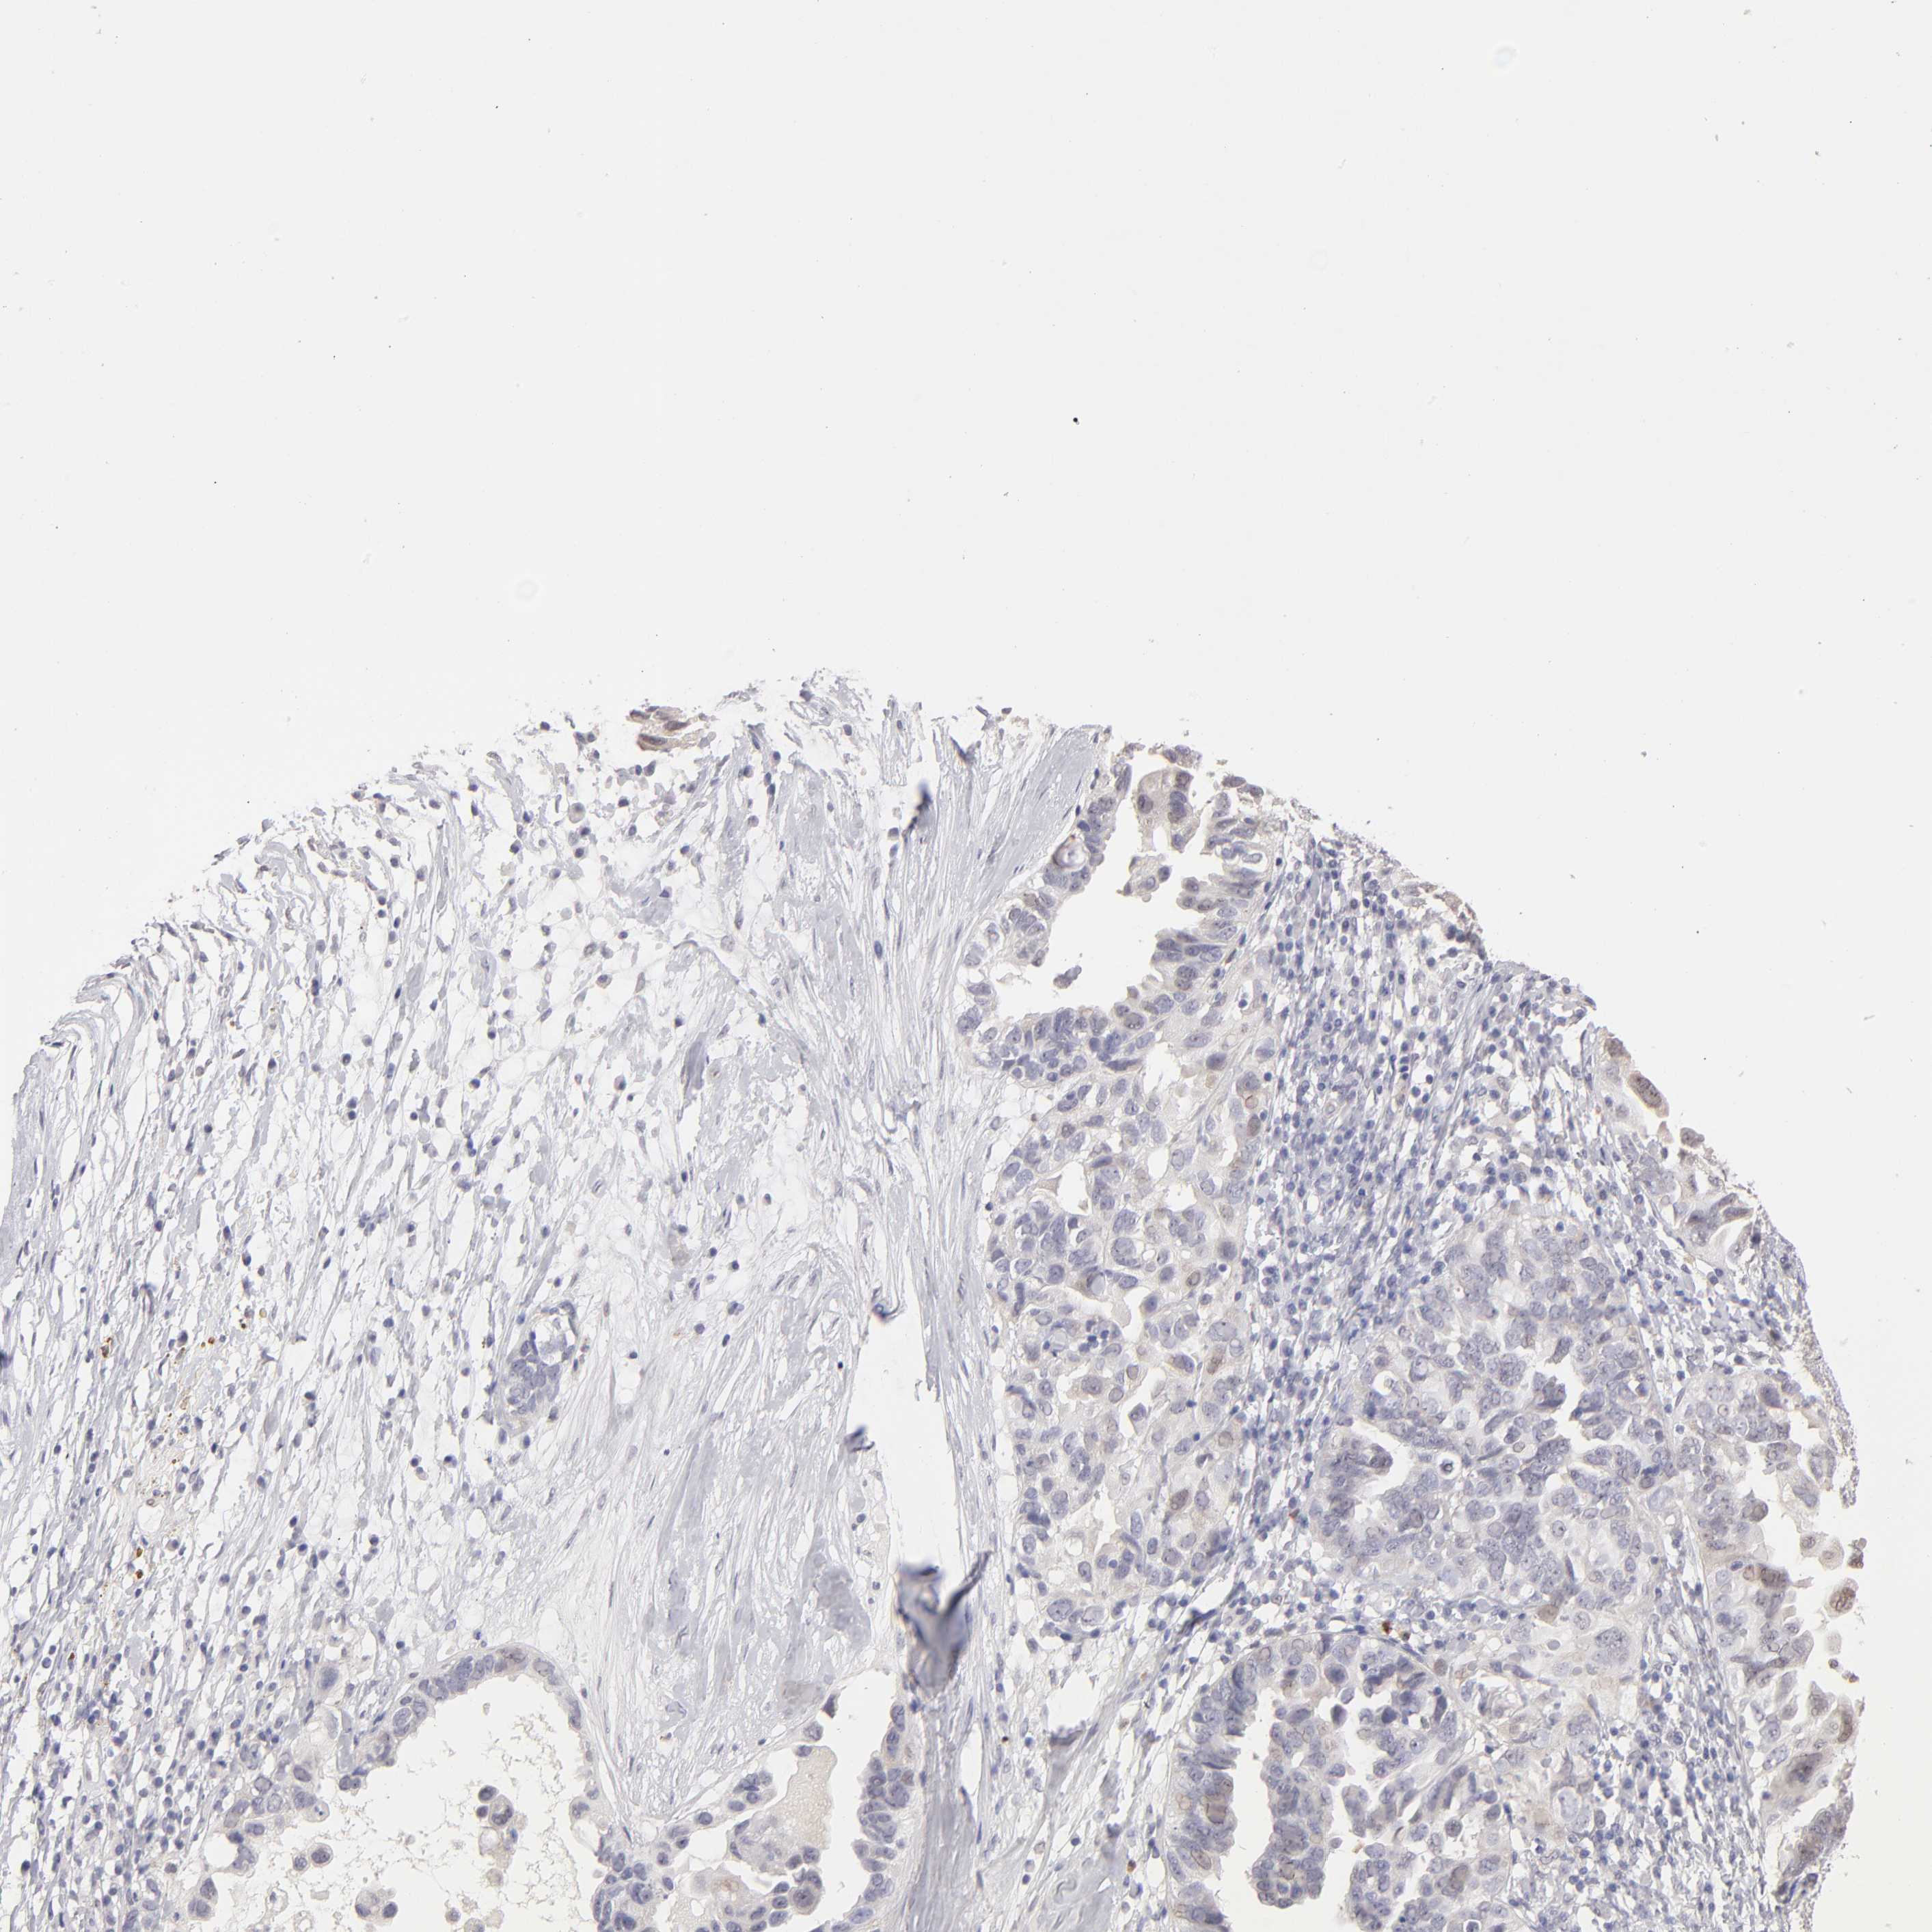

OVARIAN CANCER - Protein expressioni

A mouse-over function shows sample information and annotation data. Click on an image to view it in a full screen mode. Samples can be filtered based on level of antibody staining by selecting one or several of the following categories: high, medium, low and not detected. The assay and annotation is described here.

Note that samples used for immunohistochemistry by the Human Protein Atlas do not correspond to samples in the TCGA dataset.

Antibody stainingi

Antibody staining in the annotated cell types in the current human tissue is reported as not detected, low, medium, or high, based on conventional immunohistochemistry profiling in selected tissues. This score is based on the combination of the staining intensity and fraction of stained cells.

Each image is clickable and will lead to virtual microscopy that enables deeper exploration of all samples and also displays staining intensity scores, fraction scores and subcellular localization as well as patient and tissue information for each sample.

Antibody HPA002270

Staining

High

Medium

Low

Not detected

Intensity

Strong

Moderate

Weak

Negative

Quantity

>75%

75%-25%

<25%

None

Location

Nuclear

Cytoplasmic/membranous

Cytoplasmic/membranous,nuclear

Cystadenocarcinoma, serous, NOS

Cystadenocarcinoma, mucinous, NOS

Carcinoma, endometroid